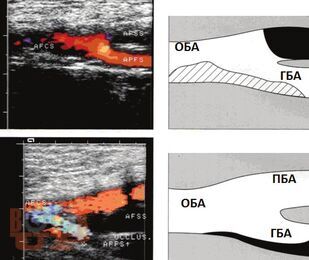

В учебном пособии дается обзор теоретических подходов, связанных с хирургической коррекцией окклюзионно-стенотических поражений в инфраингвинальном сегменте путем использования оптимального трансплантата для бедренно-подколенного шунтирования; представлены виды трансплантатов и их использование в хирургической практике.